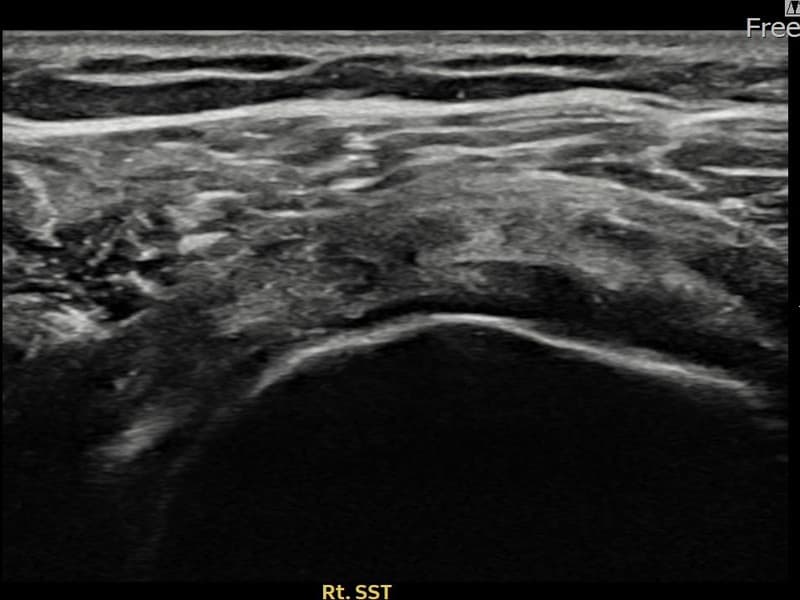

시술 전 초음파 측정 결과 파열 크기는 12mm × 7mm (힘줄 두께의 약 55% 결손)로 확인되었습니다. 시술 전 초음파에서 우측 극상근건의 광범위한 에코 단절과 힘줄 내 복합 소견이 확인되었습니다. 시술 후 초음파에서 파열 부위에 재생 조직이 형성되며 힘줄 연속성이 회복된 것이 관찰되었습니다.

50대 중반 남성 환자분으로, 우측 어깨 통증이 오래되어 파열이 상당히 진행된 상태였습니다. 다방향에서 초음파 평가를 시행한 결과 관절면측 파열이 넓게 퍼진 진행형 소견이 확인되었습니다. 파열 범위가 넓어 일반 보존 치료로는 한계가 있다고 판단하여 초음파 유도 하 축소봉합술을 시행하였습니다. 시술 후 충분한 보조기 착용 기간을 유지하고 단계적 재활을 진행하였으며, 14주 후 추적 초음파에서 파열 부위의 구조적 안정화가 확인되었습니다.